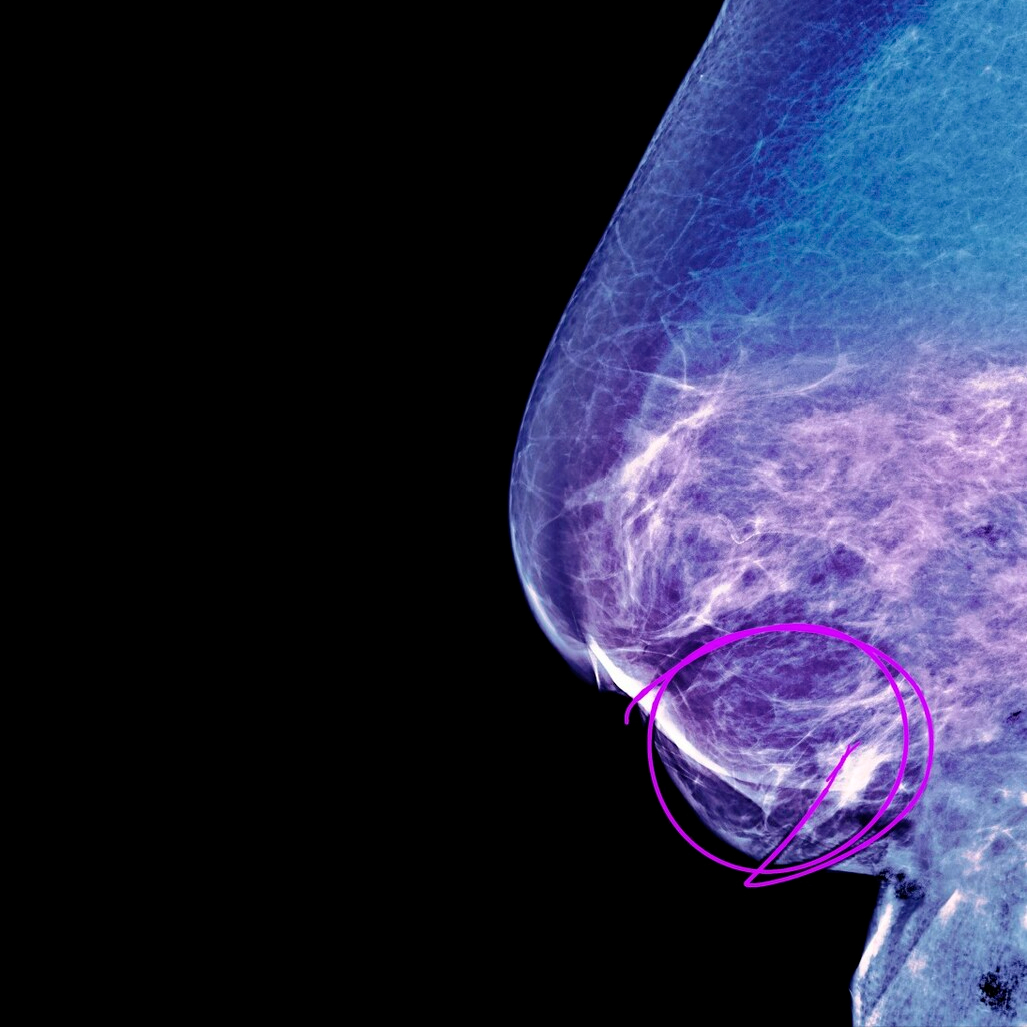

图片:图虫创意